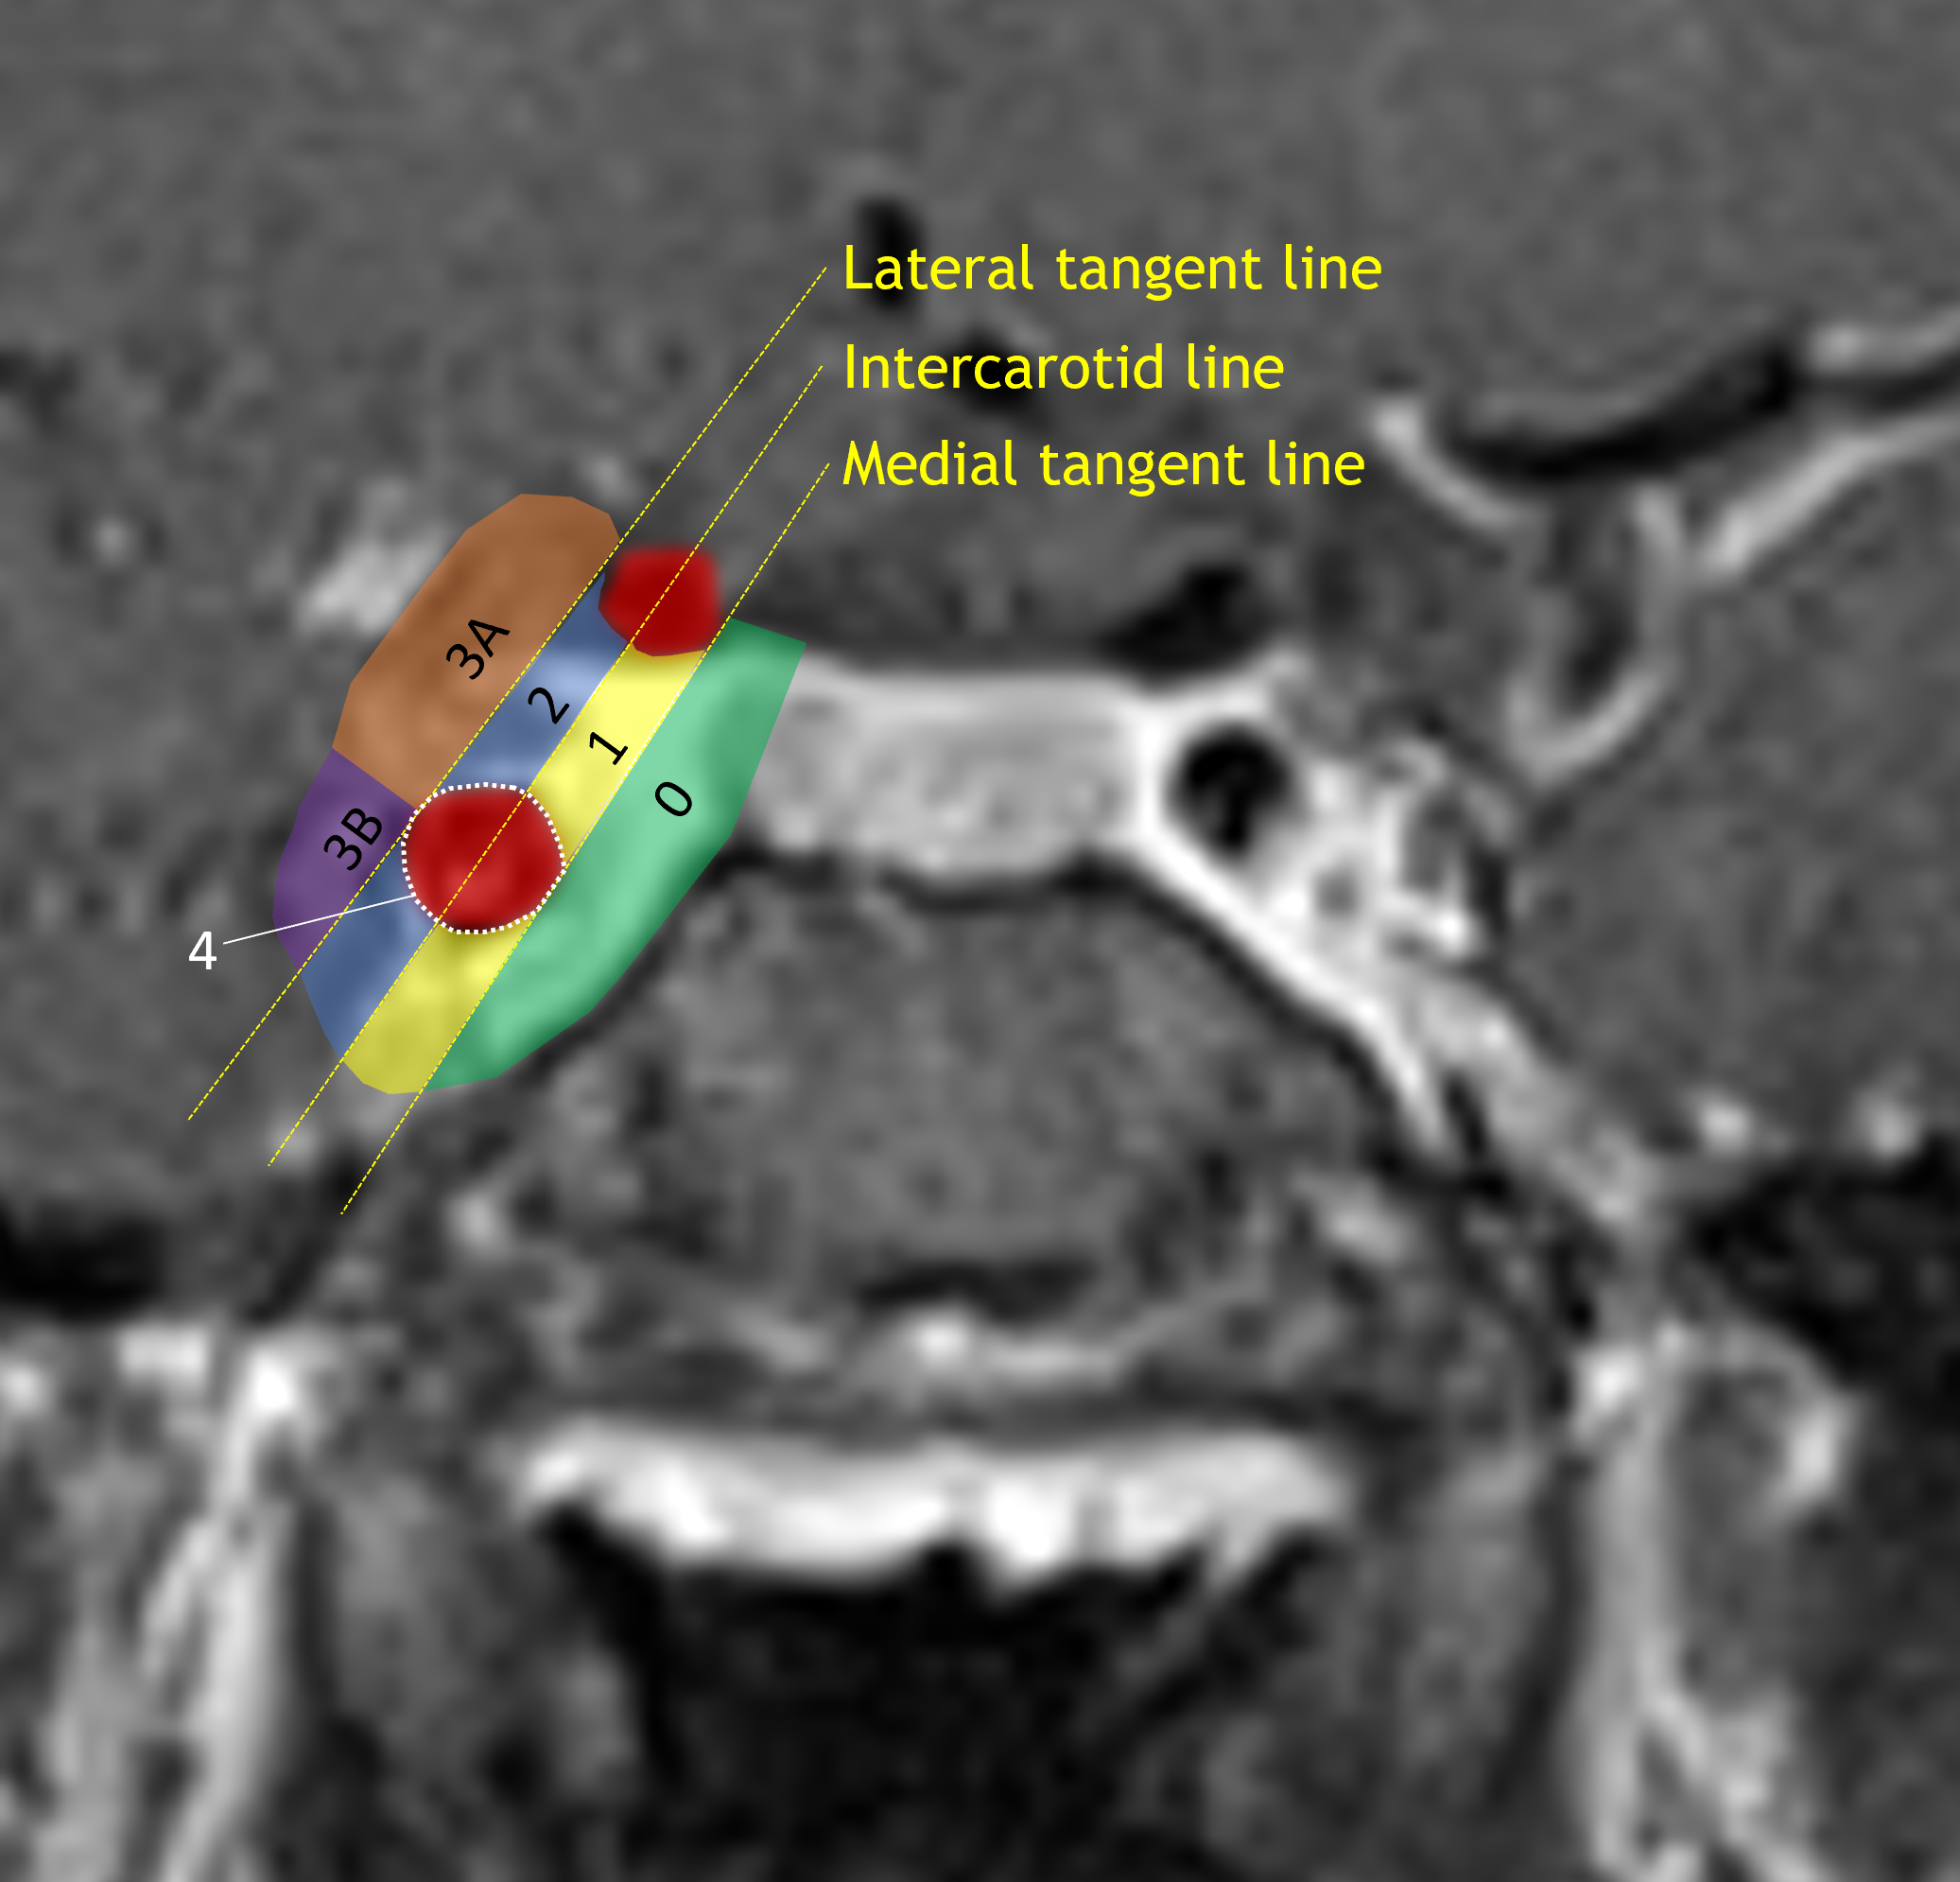

Age: 38

Sex: Male

Indication: Problems with vision

Pituitary macroadenoma